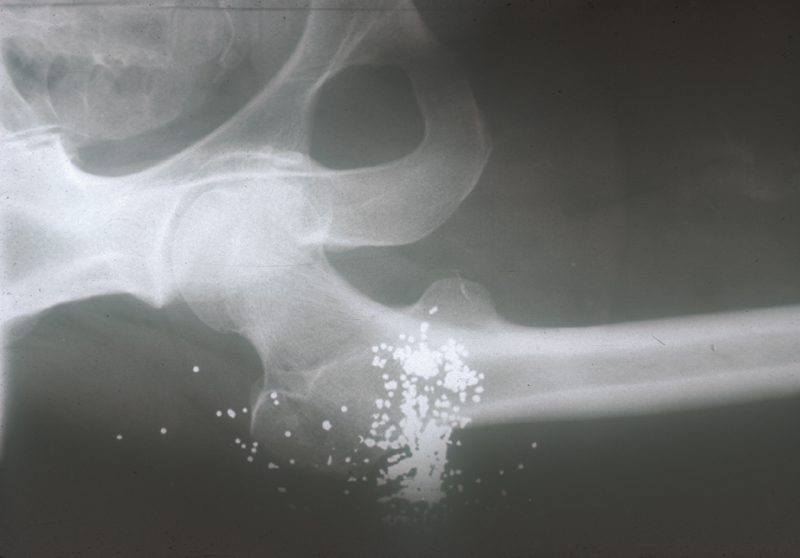

arma_fuego_cadera.JPG (211321 bytes)

Herida en cadera